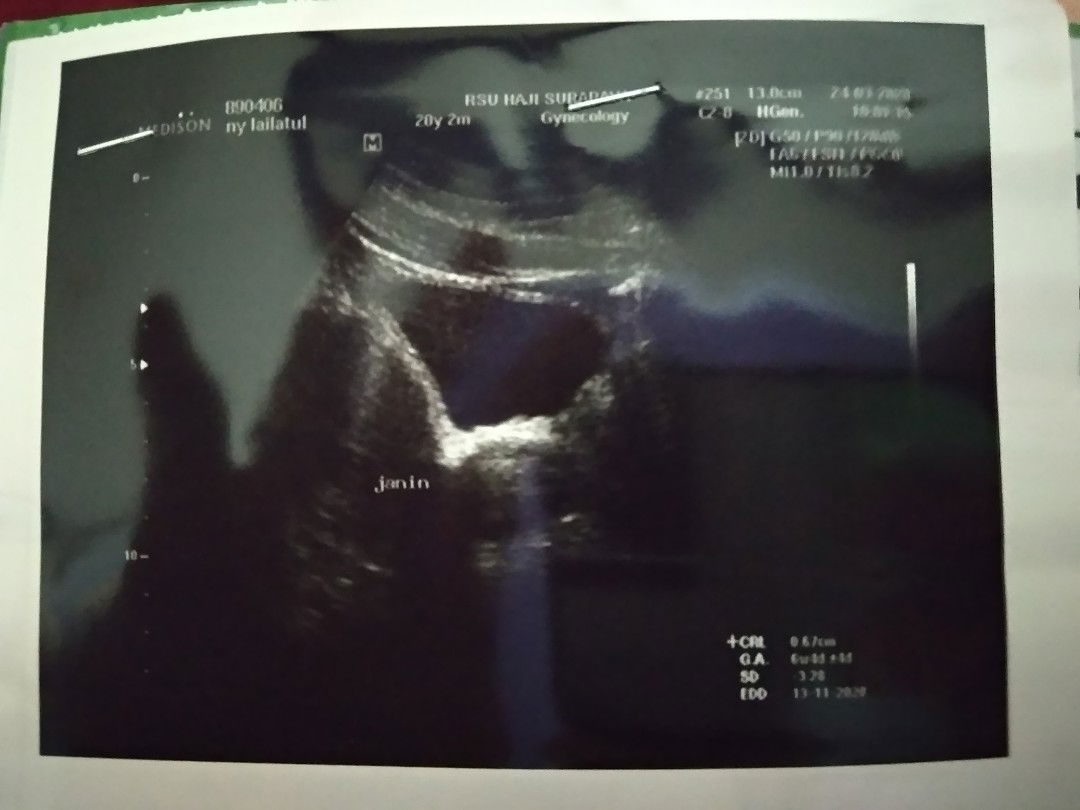

Hallo bunda saya hanya ingin bercerita saja... Kemarin hari senin tgl 13 tepat sekali saya mengalami keguguran usia kandungan baru 9 minggu 3 hari... Saya merasakan perasaan sedih yang amat sedalam-dalamnya,krna saya kehilangan calon anak .. Betapa cantiknya jika dia perempuan,dan betapa tampan jika dia laki"... Saya mengalami pendarahan yg ekstrim,dan harus di larikan ke ugd,dan ternyata harus di kiret karna msih ada yang tertinggal.. Saya tidak berhenti menangis,dan ketika dokter bilang anak yg di kandungan saya sudah tidak bisa di pertahankan,hati saya hancur bagai di sambar petir,suami dan keluarga menguatkan,dan saya hanya bisa ikhlas saja,mungkin belum rizkiku dan mungkin di balik ini semua ada hikmahnya.. Aku percaya Allah tidak tidur,dan Allah itu adil... Dan sampai sekarang saya pun masih suka nangis kalau ingat... Maaf ya bunda" kalau kata" saya mungkin ada yg bunda tidak fahami... Ini cerita pengalaman pahit yg saya alami semoga bunda" sehat dan bayinya juga sehat... Ini usg waktu bayiku baru berumur kurang lebih 1.5 bulan atau 6 minggu